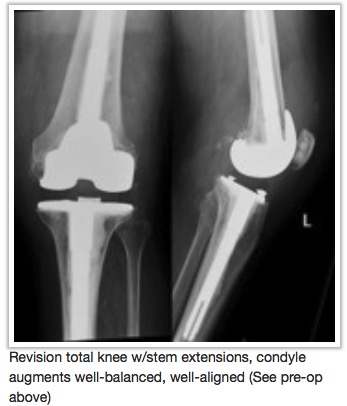

Does your knee replacement need replacing?

As people live longer and more people receive knee replacements at younger ages, it is expected that an increasing number of those implants will wear out and/or fail for some reason. In these cases, a second operation will be necessary to replace or revise the failed first replacement and this procedure is referred to as revision knee replacement. The increasing demands placed on these implants by patients in terms of longevity and durability; and expectations of patients to maintain their active lifestyles even with a knee replacement has presented a considerable reconstructive challenge to the surgeon.

left the primary knee replacement dysfunctional. Many of the common causes for failed total knee which would lead to the need for a revision of part or all of the implant are discussed on our website.